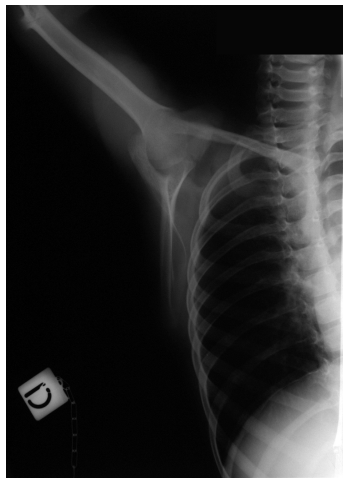

| Figure 2:specific projections of the left shoulder |

Male, 7 years and 9 months old; fell from the dad’s motorbike hitting on the floor the right shoulder. Reached the emergency room immediately after the trauma. At the clinical examination presented swelling and deep pain at the pressure on the coracoid and all over the shoulder; the motility was good but it reawaken/stirred pain in particular in abduction. The standard x-ray carried-out in the emergency room suspecting a fracture of the clavicle or humerus (figureure 1 a-b) underlined a light discontinuity at the base of the right coracoid, centering of the humeral head and continuity of the acromio-clavicular joint. Are requested the specific and comparative projections of the left shoulder (figureure 2 a-b) that highlights the separation of the coracoid base with small compound fracture. Is decided for a conservative treatment by applying Desault bandage for 25 days. At the removal, the clinic examination shows light pain at the mobilization of the shoulder and at the pressure on the coracoid. The radiographic exam points out good consolidation of the fracture and his realignment (figureure 3 a-b). At the clinic follow-up after 20 days after the removal of the bandage, the patient does not complain any pain and presents a complete motility of the shoulder.

It has a low visibility in standard x-rays [7], [1] and so it has to be researched with specific projections such as the “Stryker– notch view” [8].